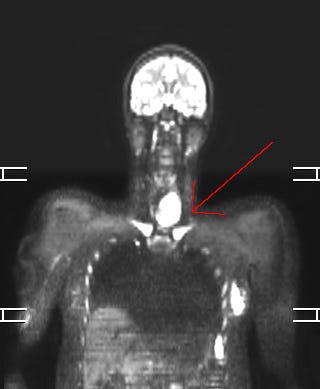

I got the full body MRI anyway a month later, in October of 2024, and they found a 6 cm tumor in my neck. That’s just a little smaller than a tennis ball. Sometimes being "difficult" or "paranoid" means being your own best advocate.